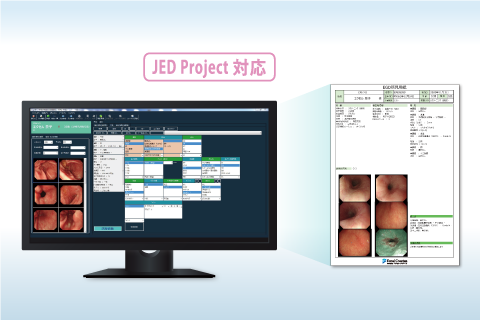

生理検査レポート JED対応 内視鏡レポート

JED対応 内視鏡レポート AI ソフト連携プラットフォーム・診断支援